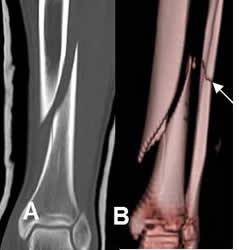

Fig 35. Fractura espiroidea.

A: TAC reconstrucción coronal y B: TAC reconstrucción 3D. Fractura espiroidea en la diafisis tibial. Adicionalmente hay fractura oblicua del peroné.